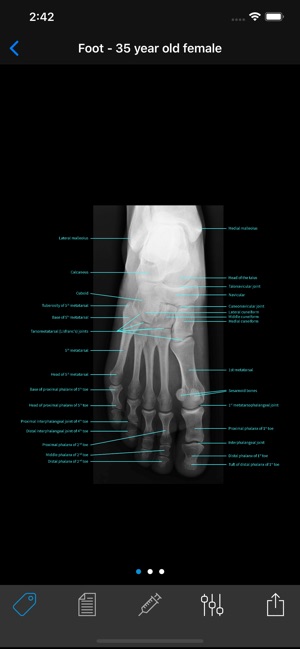

Your pocket sized x-ray reference tool. Gain confidence in x-ray interpretation with this complete atlas of radiographic anatomy, large collection of normal reference studies, and cases that include diagnoses, management and follow-up studies.

• A complete radiographic atlas of human anatomy

• 2000+ high resolution x-rays spanning patients of all ages (all x-rays have been read by board-certified radiologists)